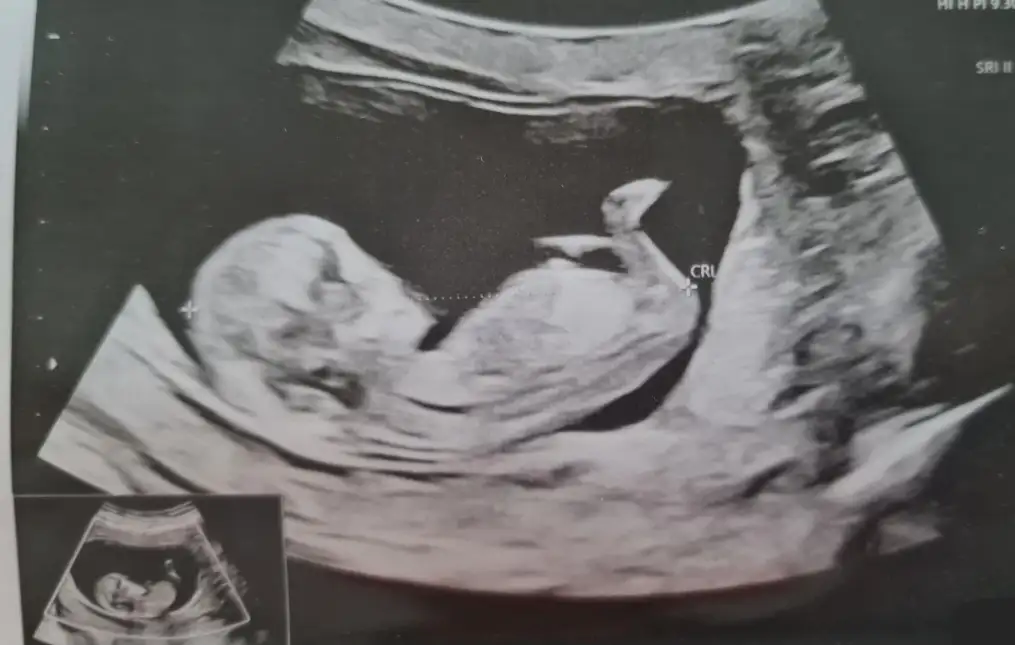

Plesanta sağ da erkek canımmerhabalar ilk bebişimiz merakla bekliyoruz6. haftanın içindeyken gitmiştik,karından ultrason tahmininizi çok merak ediyorum

teşekkür ederim inşallah sağlıkla rabbim kucaklamayı nasip etsin önceden bir düşüğüm var hep dua ediyorumPlesanta sağ da erkek canım

Selaaammm rica etsem benim bebişimede bakarmısınPlesanta sağ da erkek canım